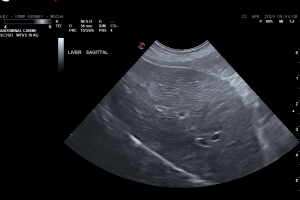

Signalment: 4y FI Miniature Australian Shepherd CC: acute vomiting, lethargy, and anorexia. PE: icteric; dehydrated; CBC/chem: Hyperbilirubinremia, increased liver enzyme activity, marked leukocytosis, hypokalemia and hyponatremia. Leptospirosis PCR and …